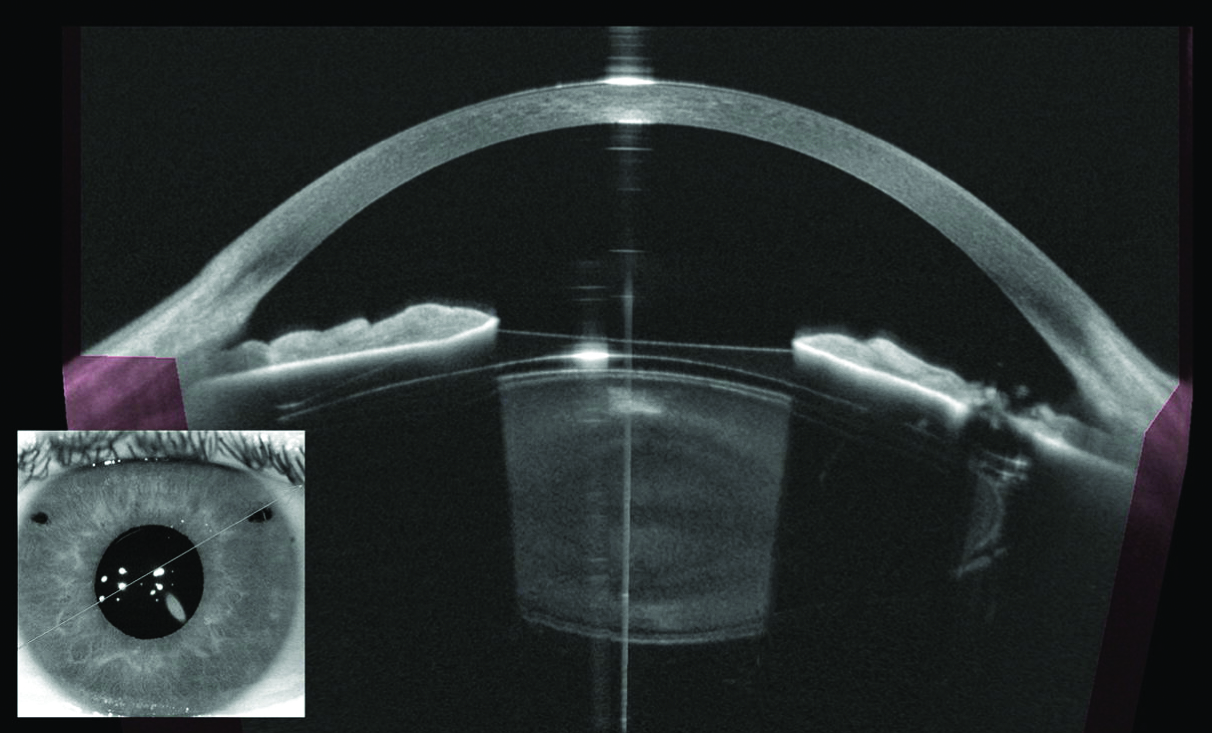

The Oct Eye device utilizes light waves to capture high-resolution, cross-sectional images of the retina. Imagine slicing a piece of cake to see all the layers perfectly; the Oct Eye does this for your eye, but without touching it!

Unlike standard photography, which just captures the surface, OCT produces detailed images of tissue structures underneath the surface. This allows doctors to measure the thickness of the nerve fiber layer and retina with extreme precision. These measurements are crucial, as subtle changes in thickness can signal the very beginning of serious eye diseases.

Furthermore, this technology doesn't just provide static pictures; it creates topographic maps. These maps help track changes over time, giving your eye care professional an invaluable tool for personalized treatment planning and monitoring disease progression.

The device sends out a beam of light toward the eye. When this light hits different layers of tissue—like the photoreceptors or the underlying blood vessels—it reflects back. The scanner then measures how long it took for the light to return.

By measuring the 'echo' time of the light, the machine reconstructs a detailed 3D image of the eye's internal structures. This process is incredibly fast, typically taking only a few seconds per eye, and it is completely safe and painless.

In short, the precise timing of the returning light waves allows the Oct Eye machine to differentiate between healthy, standard tissue and areas showing early signs of swelling, thinning, or fluid accumulation.